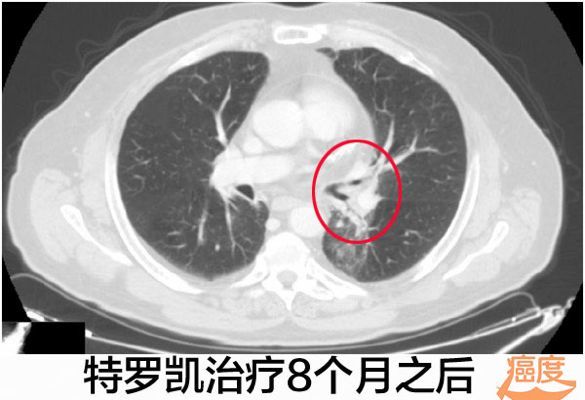

:化疗失败的EGFR阴性肺腺癌使用特罗凯病灶完